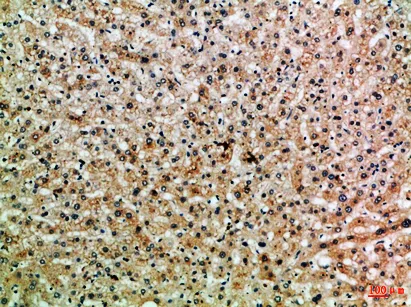

C3aR Rabbit Polyclonal Antibody($99/20μL)

Cat: APRab07746

Size1:20μL Price1:$99

Size2:50μL Price1:$118

Size3:100μL Price2:$220

Size4:200μL Price3:$380

Application:IHC-P,IF-P,IF-F,ICC/IF,ELISA

Reactivity:Human,Rat,Mouse

Conjugate:Unconjugated

Optional conjugates: Biotin, FITC (free of charge). See other 26 conjugates.

Gene Name:C3AR1